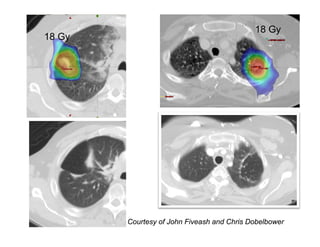

In Vivo Dosimetry at UAB? In Vivo Dosimetry at UAB? • 15‐20 Gy x 3 in 40 patients 15 20 Gy x 3 in 40 patients • ~75% treated for secondary metastases • 4D CT simulation with abdominal  l h bd l compression – PTV = gated ITV plus 5 mm – < 5 mm tumor motion then no gating – Gated KV or CBCT image guidance – Most commonly 7‐13 beams Courtesy of John Fiveash and Chris Dobelbower

18 Gy 18 Gy Courtesy of John Fiveash and Chris Dobelbower